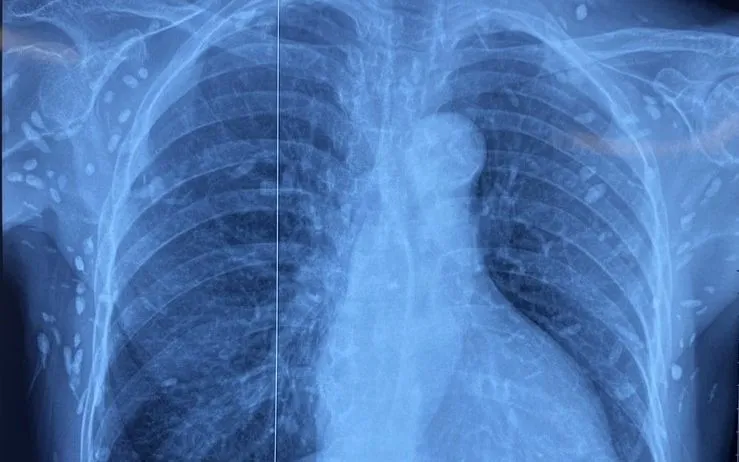

Nhiều nốt cản quang dưới da thành ngực-bụng và chi trên.

Người bệnh được chuyển đến Viện Lâm sàng các bệnh Truyền nhiễm trong tình trạng rối loạn ý thức, đe dọa suy hô hấp. Kết quả chụp cắt lớp vi tính sọ não và X-quang ngực - bụng cho thấy rất nhiều nốt cản quang nằm rải rác trong nhu mô não và dưới da vùng ngực, bụng, tay. Một số u cục có thể sờ thấy bằng tay.